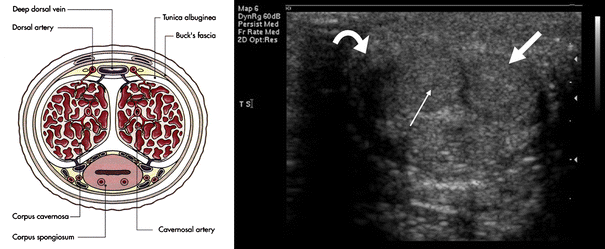

Irrespective of the indication for penile ultrasound routine scanning during penile ultrasound should include both transverse and longitudinal views of the penis by placing the transducer probe on the dorsal or ventral aspect of the penis. Treatment consists of noninvasive low-intensity sound waves that pass through erectile tissue restoring natural erectile function by clearing plaque out of blood vessels and encouraging the growth. Erectile dysfunction cannot be diagnosed solely on the basis of a penile ultrasound examination.

Pharmaco Penile Duplex Ultrasonography in the Evaluation of Erectile Dysfunction J Clin Diagn Res. Penile Duplex Ultrasound for Detecting Vascular ED Penile abnormalities ie some plaques of Peyronies disease fractures of the corpora cavernosa thickening of the tunica albuginea and septum may be easily displayed by B-mode investigation in the flaccid state. Erectile dysfunction is a common condition.

It is used to determine the integrity of the vascular mechanism. Erectile dysfunction ED by penile dynamic colour-duplex Doppler ultrasonography D-CDDU is actually considered a second level approach to ED patients because of the fact that intracavernous injections test IV with prostaglandin-E.